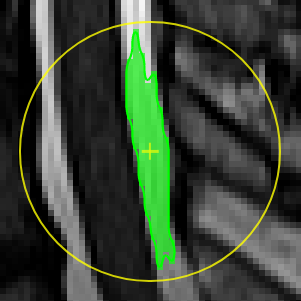

On the left panel of the ROI-tool the current type of pen mode (pen type) and the size of the pen can be set. You can turn on "live preview" to see what the current pen would draw. Displayed opacity of the ROI can be determined and whether outlines are drawn. The available pen types are as follows:

Unconstrained 3D region Growing.

Select a pixel by keeping left mouse button pressed. By moving the mouse left/right (while mouse pressed) the similarity threshold can be changed.